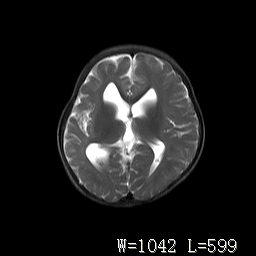

标题: PED3252:脑室增大。

女,3岁,3岁不会说话,阵发性抽搐、自伤。

考虑为梗阻性脑积水(中脑导水管狭窄)。

侧脑室不规则,前后角尖角样,脑白质较少:考虑灰质发育不良可能

考虑,脑发育不良,胼胝体发育不全?(图片不全,矢状位?)